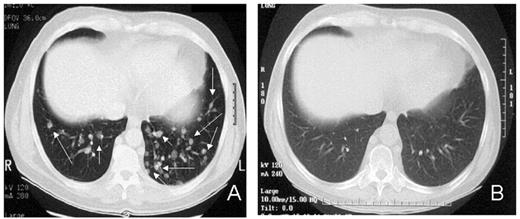

Renal Cell Carcinoma (RCC): Regression of treatment-refractory metastatic solid tumors following nonmyeloablative HCT has recently been described in a number of different tumors. We chose to first test for GVT effects in metastatic melanoma and RCC because these tumors are considered “immuno-responsive.” Furthermore, both are resistant to chemotherapy, and once metastatic, offer virtually no chance for long-term survival. Patients received conditioning with cyclophosphamide (60 mg/kg x 2 days) and fludarabine (25 mg/m2 x 5 days), followed by infusion of unmanipulated, G-CSF mobilized peripheral blood hematopoetic cell grafts from 6/6 or 5/6 HLA-matched sibling donors. Decisions regarding the timing of GVHD prophylaxis withdrawal were based on disease status and T-cell chimerism.18 Patients with stable disease and full donor T cell chimerism on day 30 initiated a 6-week cyclosporine taper beginning 2 months after the transplant. In contrast, those with mixed T-cell chimerism or disease progression had their cyclosporine withdrawn earlier.

RCC was quickly identified as a target for a GVT effect.31 Ten of the first 19 patients had disease responses including 7 partial and 3 complete responses.32 The first patient treated remains without evidence of disease 5½ years after transplantation (Figure 9 ). Remarkably, all responding patients had failed prior treatment with cytokine-based therapy. Disease responses occurred mostly commonly in patients with pulmonary-restricted metastatic disease, although regression of bulky tumors in multiple metastatic locations has occasionally been observed. Disease responses were typically delayed, occurring 4 or more months after the transplant only after T-cell chimerism had converted from mixed to full donor in origin. Representative lineage, specific engraftment profiles, and their relationship to clinical outcome are shown in 2 patients who underwent nonmyeloablative transplantation and had graft-versus-RCC effects (Figure 10 ). Although GVHD was favorably associated with a disease response (Figure 11 ), some patients had dramatic regression of metastatic disease without having acute or chronic GVHD. Disease progression in the first few months after the transplant did not necessarily preclude a GVT effect; a unique pattern of tumor growth followed by subsequent disease stabilization or regression was observed in several patients. Furthermore, some patients who did not respond to cyclosporine withdrawal had tumor shrinkage after a donor lymphocyte infusion or following treatment with low-dose subcutaneous interferon-alpha.